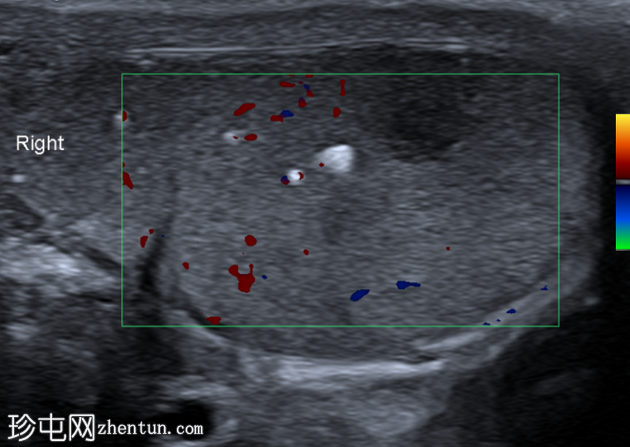

横切面

右侧睾丸内可见一异质性肿块,大小约10 x 14 x 15 mm,包含实性和囊性成分。肿块内可见多发小钙化灶。彩色多普勒超声检查显示肿块内血流信号较少。